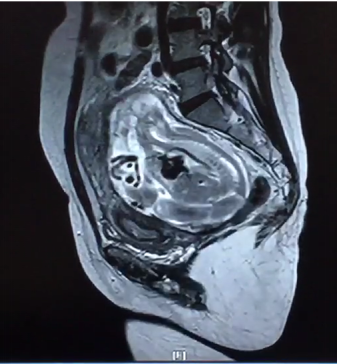

2月24日,我院产科、泌尿外科、麻醉手术科、胃肠外科、输血科等多学科合作成功救治一名腹腔妊娠特殊患者。这是我院多学科合作战胜疑难杂症的又一成功案例。近年来,作为三级甲等综合医院,亚洲色吧 附二院始终坚持以患者为中心,充分发挥综合医院的优势,积极探索研究,持续加强学科建设,不断拓展多学科合作的广度和深度,利用多学科合作为人民群众解决了很多疑难杂症,用实际行动巩固脱贫攻坚成果,助力乡村振兴,为维护人民群众的健康持续奋斗。